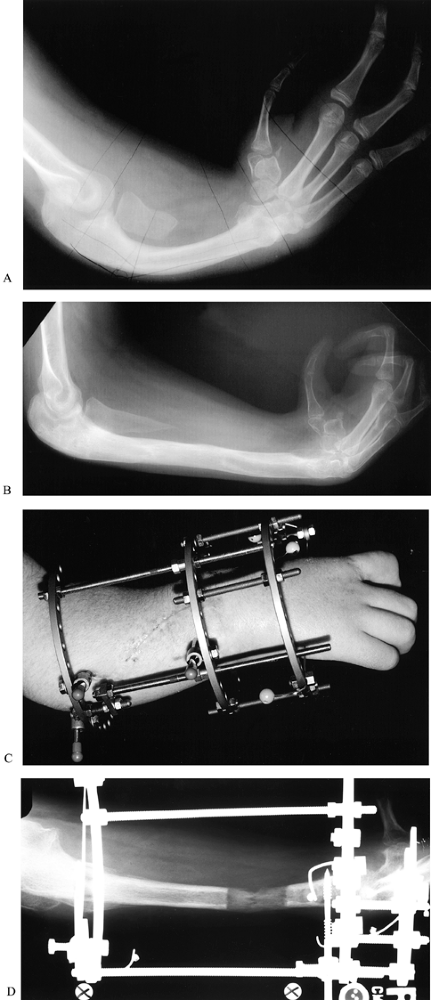

![]() |

Figure 69.8. Index pollicization (this patient has already undergone centralization of the carpus on the ulna; see Fig. 69.48). A: Preoperative palmar view. B: Preoperative dorsal view. C: Postoperative palmar view. D: Postoperative palmar view.

Figure 69.9. Index pollicization (different patient from the one shown in Fig. 69.8). A: Tip pinch using new thumb. B: Tip pinch showing pronation of new thumb. C and D: Grasp using new thumb.

argue for pollicization in the second 6 months of life, to allow the

index finger functions like a thumb (124), but the base is less mobile and stable; the appearance is usually quite satisfactory (Fig. 69.8 and Fig. 69.9).